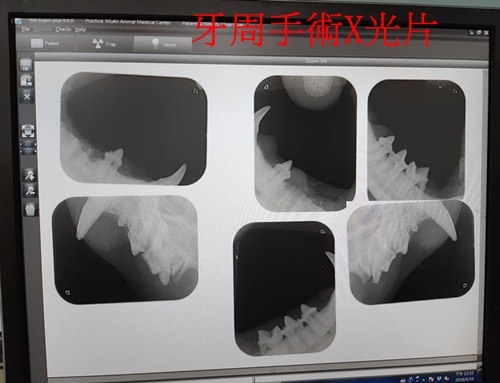

牙周手術 沐恩

醫師說明

拐拐的口炎很嚴重,有增生組織,通常口炎嚴重的貓咪多數會建議後面臼齒全拔,但因照X光結果除了最後一顆牙之外其他牙根都很好,所以今天沒有全拔,主要是處理口腔後段部份的牙齒,中段之前的牙都還留著。

上下各留一顆小的臼齒讓牠可以叼食物,但用來咬碎就比較沒辦法,主要用來咬碎的大臼齒,下方拔兩顆只留一顆,因為若留下並排的牙,有牙縫容易有細菌怕再發炎,下方兩顆大臼齒因離發炎處近所以就全拔掉,有一側因為較難拔有剝開牙齦再縫合。